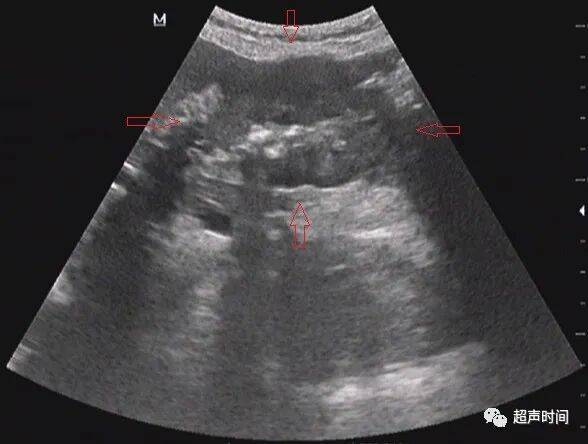

图 4 胃窦横切呈「假肾征」,提示胃壁异常增厚